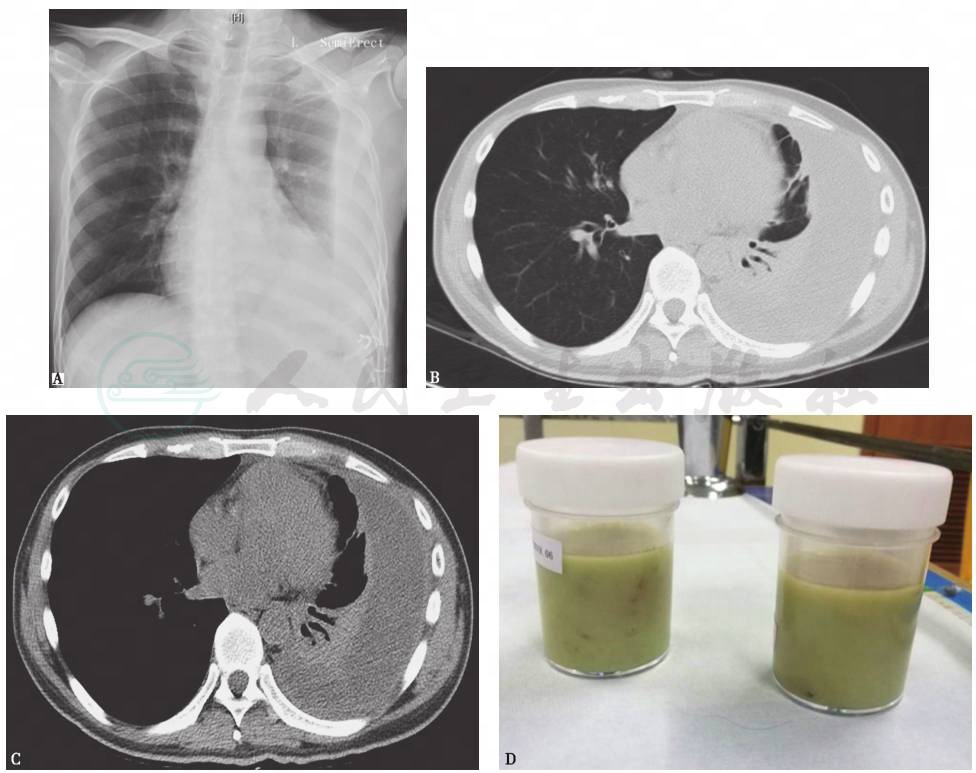

图5 化脓性胸膜炎的影像学特点

男性,34岁,肾移植术后3周,发热、咳嗽、咳痰6天。胸部X线片显示左侧大量胸腔积液(A),胸部CT显示左侧胸腔积液伴胸膜肥厚(B、C)。胸腔积液可见脓性外观(D)。胸腔积液生化检测结果:TP 43.1g/L,LDH 6769U/L,血糖0.59mmol/L,ADA 80.4U/L

引自:呼吸系统疑难病例诊疗辨析.第1版.ISBN:978-7-117-26415-0.主编: